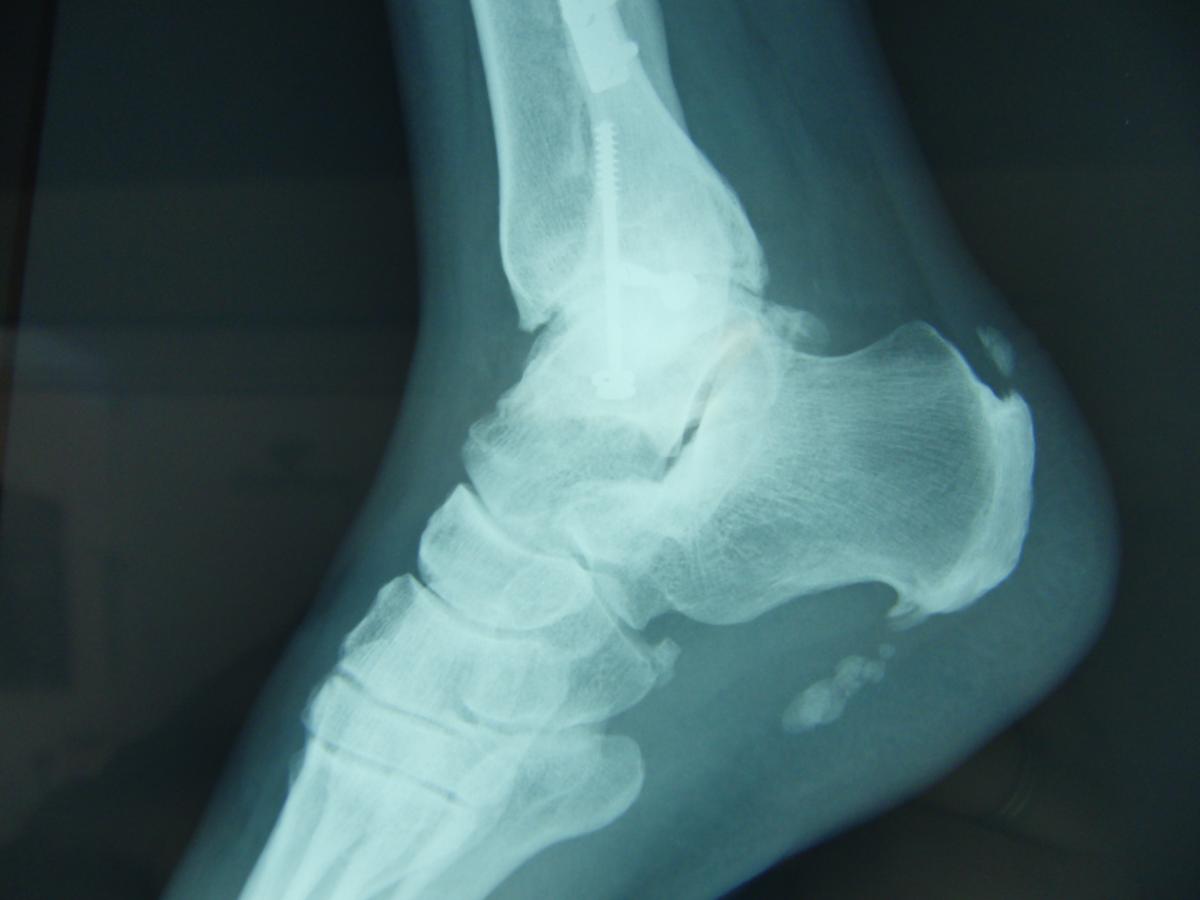

Fascitis Plantar Espolon Calcaneo Operacion, Fascitis Plantar: Cirugia Minimamente Invasiva, 1.19 MB, 00:52, 395,353, Juan Arnal, 2018-03-23T17:28:29.000000Z, 3, Espolón Calcáneo y Fascitis Plantar Cirugía por Mínima Incisión (MIS, www.youtube.com, 1280 x 720, jpeg, WebEl espolón calcáneo es una protuberancia ósea, frecuentemente con forma de nervio, que aparece en la parte inferior del hueso calcáneo. Es habitual que se produzca una. WebEl espolón calcáneo es la calcificación producida en el tubérculo posterointerno del hueso calcáneo, esta patología cursa con dolor local al caminar. WebEl espolón calcáneo, también llamado espolón, suele deberse a una artrosis o puede ser una degeneración de la fascitis plantar. A menudo se necesita una., 20, fascitis-plantar-espolon-calcaneo-operacion, Novedades y Muebles WebEl espolón calcáneo es una protuberancia ósea, frecuentemente con forma de nervio, que aparece en la parte inferior del hueso calcáneo. Es habitual que se produzca una. WebEl espolón calcáneo es la calcificación producida en el tubérculo posterointerno del hueso calcáneo, esta patología cursa con dolor local al caminar. WebEl espolón calcáneo, también llamado espolón, suele deberse a una artrosis o puede ser una degeneración de la fascitis plantar. A menudo se necesita una.

WebEl Espolón Calcáneo es una patología recurrente y es un crecimiento óseo situado en la parte inferior del calcáneo provocado por una inflamación de la fascia que es una. WebFasciitis Plantaris Una inflamación en la planta del pie, más precisamente, en la base del tendón plantar al hueso del talón. Como consecuencia de una inflamación a largo plazo,.

WebYa hemos dicho que un espolón en el talón es una excrecencia anormal del hueso calcáneo en la parte posterior del talón causada por el exceso de tensión o tracción. WebEl espolón calcáneo es una prominencia de hueso que se produce por una fascia plantar que ha funcionado de manera alterada durante mucho tiempo, produciendo que el punto. WebExisten múltiples técnicas para tratar este tipo de patologías, especialmente la fascitis plantar, sin embargo, debido al desarrollo óseo que posee el espolón calcáneo el. WebPara combatir la fascitis plantar y espolón calcáneo es crítico llevar calzado que tenga una plantilla que ofrezca amortiguación y no esté gastada en el talón. También es importante. WebLa fascitis plantar y el espolón calcáneo son una de las causas más frecuentes de dolor en el talón, siendo un dolor muy típico en los primeros pasos del día al levantarse de la. WebLa incidencia del espolón calcáneo plantar aumentó con la edad; el 41,8%, correspondían a pacientes con más de 70 años, mientras que no hubo asociación. WebPero ¿Qué es la fascitis plantar y el espolón calcáneo? La fascitis plantar consiste en la presencia de microrroturas en la fascia derivadas de traumatismos constantes,. WebEl tratamiento de la fascitis plantar es casi siempre conservador, y encaminado en primer lugar a quitar la inflamación que provoca el dolor y en segundo lugar a intentar corregir.

WebEspolón Calcáneo y Fascitis Plantar Cirugía por Mínima Incisión (MIS) Espolón Calcáneo y Fascitis Plantar Cirugía por Mínima Incisión en régimen ambulatorio y con anestesia local. WebLa fascia plantar participa en el mecanismo de Windlass mediante el sistema Aquileo-Calcáneo- Plantar. Los dos son sistemas muy importantes para realizar una dinámica de. WebNo se debe al Espolón Calcáneo sino al proceso inflamatorio que se produce en el punto de rotura de la fibra de la fascia plantar. Primero, hay los llamados "dolores iniciales", cuyo.